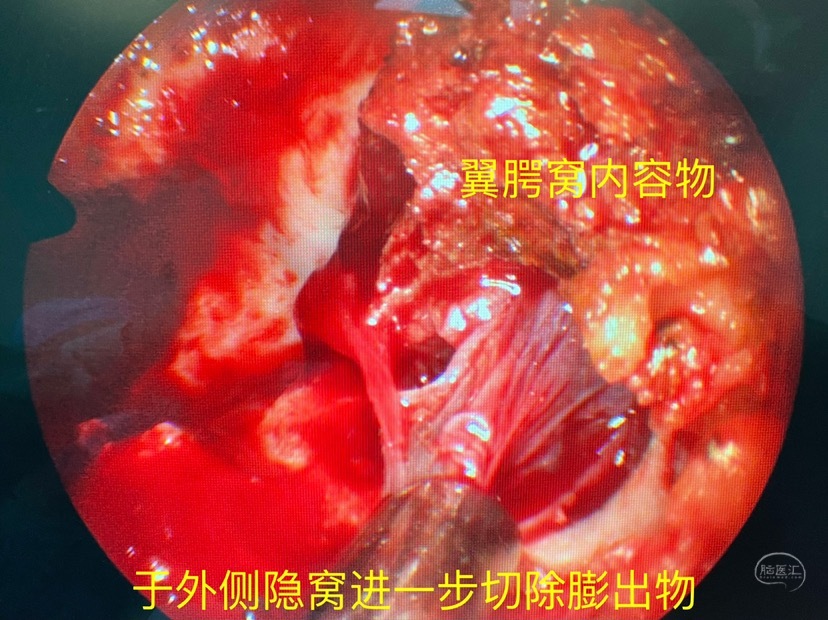

进一步切除膨出物并寻找漏口